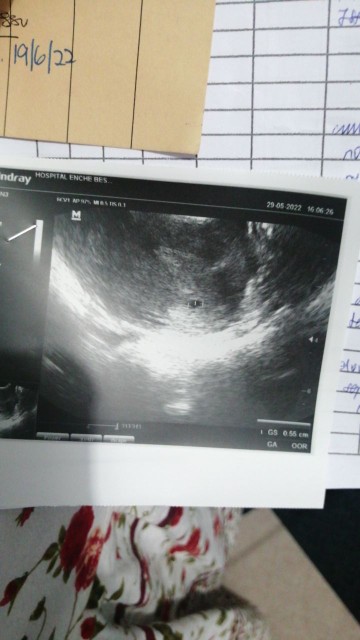

saya baru scan semalam... 6minggu... Alhamdulillah kantung dalam rahim. tapi tak nampak apa lagi sebab kecik lagi... 21.37mm

Sy pn scan smlm n xnmpk. But i just wanna make sure my baby dlm kantung bkn luar rahim. N doc ckp smlm dh ade heartbeat 🥰💓

Boleh ☺️ tapi hanya nampak kantung belum nampak baby. I also scan at week 6 for confirmation pregnancy.